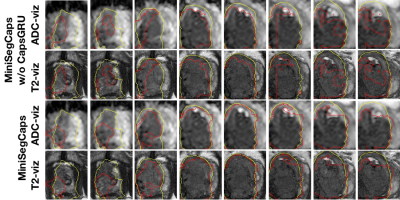

Fig.3 illustrates a visual comparison of the cropped T2, cropped ADC, cropped zonal mask, lesion ground truth, and predicted lesion mask by MiniSegCaps on T2 and ADC images. Our model successfully produced satisfactory segmentation of prostate cancer and revealed the spatial relationship between the zonal mask, lesion on T2, and ADC, which might help lesion location and classification. We also obtained consistent segmentations across adjacent slices within one volume, as shown in Fig.4. Our MiniSegCaps obtained better results than MiniSegCaps w/o CapsGRU, which indicates that CapsGRU captured the spatial information across adjacent slices as expected, boosting the prostate cancer segmentation performance. Moreover, our model achieved acceptable performance on BPH segmentation as shown in Fig.6.

Fig. 4. Visualization of lesion segmentation results on eight slices from one case. The yellow contour is ground truth, and the red contours are predictions from the MiniSegCaps without or with CapsGRU. MiniSegCaps with CapsGRU can better delineate the prostate cancer contours across different slices in one case compared to that without CapsGRU.